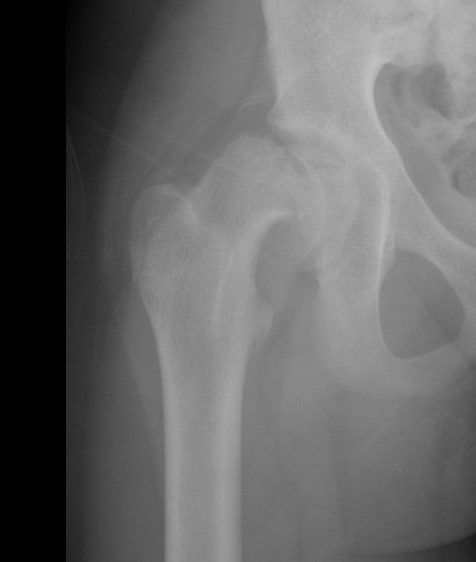

Deformity

Varus / extension / external rotation

Osteotomy

Valgus / flexion / internal rotation